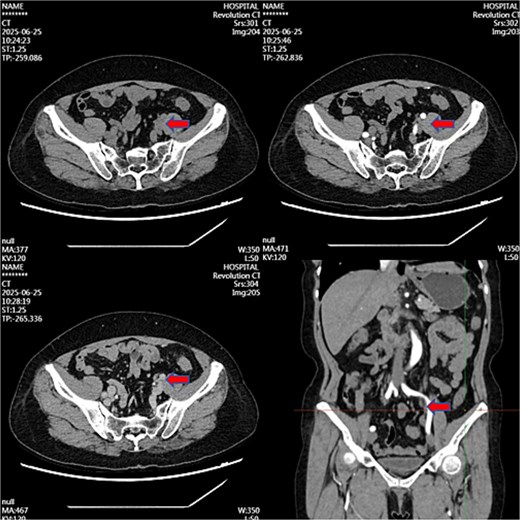

Serial monitoring documented:

Month 3: 60% volume reduction.

Month 12: 4 mm residual mass (ureteral stent removed at 10 months postoperatively).

Month 36: Near-complete resolution (Fig. 3).

Contrast-enhanced CT image at 36-month follow-up demonstrating near-complete resolution of previously described left iliac vessel mass following medical therapy.